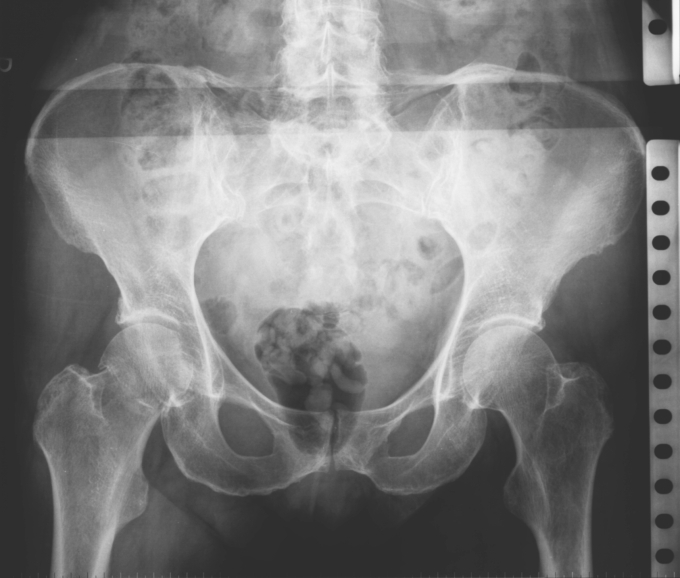

56 year old patient with dyspagia. A tumor of soft tissue was described in upper mediastinum on plain X-ray of the thorax. What is this mass in the upper mediastinum?